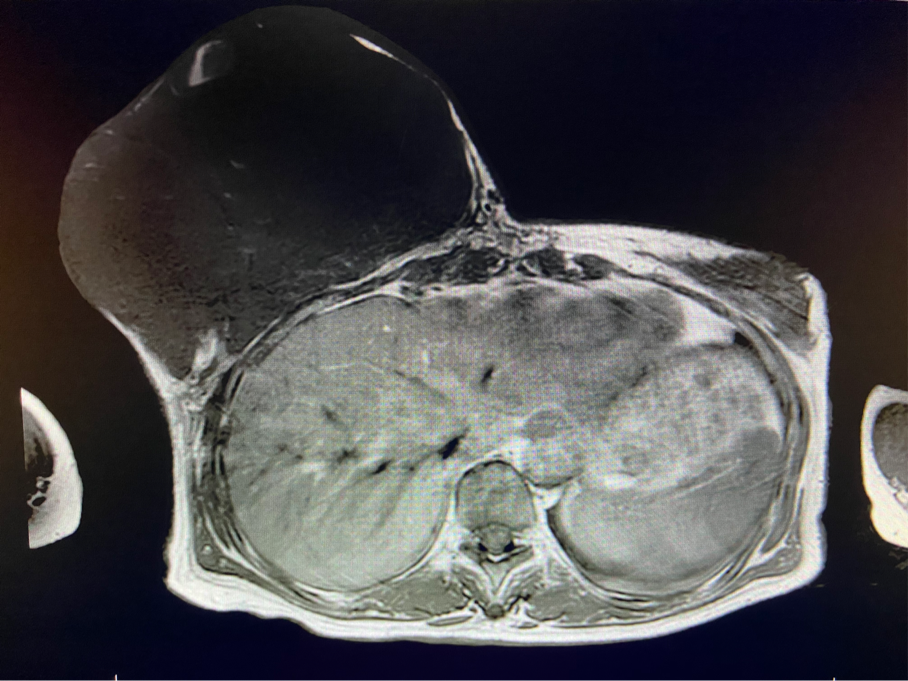

王女士終于可以暢快呼吸、正常走路了,不用再擔(dān)心壓在胸前令人窒息的腫瘤和別人異樣的眼光。近日,王女士在西安國(guó)際醫(yī)學(xué)中心醫(yī)院甲乳外科接受了右乳全乳切除術(shù) 胸壁皮瓣成形術(shù)或植皮術(shù),切除了胸口重達(dá)5斤的腫瘤。

6個(gè)月前,王女士能感覺到右乳腫物明顯增大至“鴨蛋”一般,而且伴有局部皮膚瘙癢及輕度脹痛,可這次王女士并沒有那么幸運(yùn),服藥3個(gè)月不僅沒有控制住腫物,脹痛也越發(fā)嚴(yán)重,超聲檢查提示:右乳囊實(shí)性占位,最大前后徑約10.8cm,右腋窩多發(fā)腫大淋巴結(jié),遂行右乳腫物穿刺活檢術(shù),術(shù)后病理檢查提示:右乳腫物穿刺乳腺組織2條,均可見導(dǎo)管囊性擴(kuò)張,部分區(qū)域間質(zhì)纖維增生,其中1條內(nèi)導(dǎo)管上皮成普通型增生。輾轉(zhuǎn)當(dāng)?shù)囟嗉裔t(yī)院藥物治療后,錢沒有少花,但是療效甚微。

2周前,王女士的右乳外下方皮膚破潰,伴大量滲液,還發(fā)出陣陣惡臭。經(jīng)多方打聽,王女士從外地來到西安國(guó)際醫(yī)學(xué)中心醫(yī)院甲乳外科劉曉敏主任處就診。入院后,迅速完善了一系列相關(guān)術(shù)前檢查:王女士的雙乳外形不對(duì)稱,右乳約22?20cm,皮膚水腫明顯并可見靜脈曲張。右乳外下象限皮膚可見局部破潰,創(chuàng)面有3處,共約6?4cm大小,創(chuàng)面呈暗紅色,伴有血性滲出及惡臭,局部皮膚溫度升高。右側(cè)腋窩可觸及腫大淋巴結(jié)。

該患者右乳巨大腫物術(shù)前初步考慮乳腺葉狀腫瘤可能,因腫瘤太大,幾乎遍及整個(gè)右側(cè)乳房,為保證“無瘤原則”,術(shù)中切除范圍位置未知,極有可能出現(xiàn)皮瓣缺損。于是,經(jīng)過和整形醫(yī)院郭樹忠院長(zhǎng)、整形外科王愛武主任的討論,提供了兩種手術(shù)方式,一是創(chuàng)面修復(fù)(植皮或轉(zhuǎn)移皮瓣修復(fù)創(chuàng)面),二是乳房再造,與患者及家屬溝通后,決定先解決腫物,3年病情不再?gòu)?fù)發(fā)后,可以再考慮乳房重建。